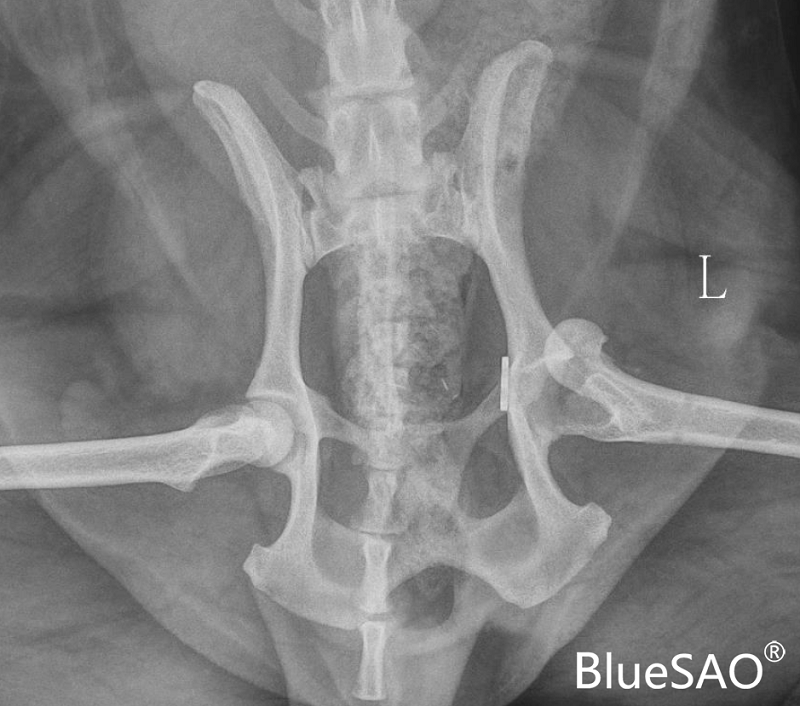

博美犬,6岁,雄性,体重8.6Kg(超级肥胖)。

因左侧股骨头脱臼,圆韧带再造断裂史,决定进行髋关节置换。术中使用BlueSAO佰陆小型骨水泥型髋关节系统进行置换,植入物采用:14mm髋臼杯、2号股骨柄、8mm(+0)的股骨头。手术顺利完成,期待早日康复!

术前X光片: